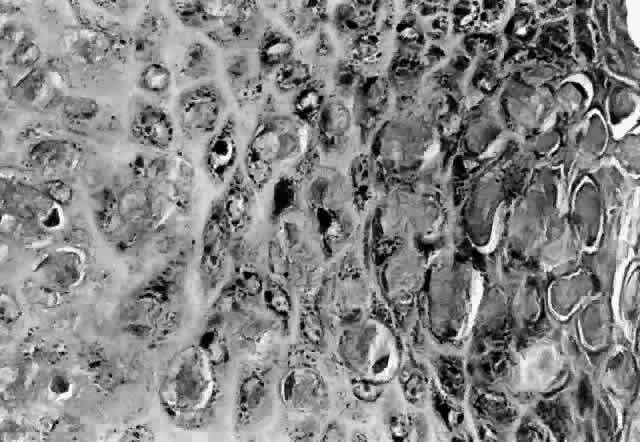

HPV-induced conjunctival squamous papillomas demonstrate papillomatosis, acanthosis, and koilocytosis (Fig. 6). Because they are mucous membrane lesions, those of the conjunctiva and lacrimal sac show no granular cell layer but will show keratinization if they are large or exposed (Fig. 7). In our experience the frequency of koilocytes is variable, even in lesions almost certain to be viral (Fig. 8). Scattered inflammatory cells may be present in the cores or epithelium. Virus can be detected immunohistochemically in the nuclei of the cells (Fig. 9).

Early dysplastic lesions (conjunctival intraepithelial neoplasia) show thickened epithelium with extension of basal-like cells beyond the basal layer, but cells continue to mature into flat squamous cells. Mitoses are also seen higher in the epithelium. As the degree of dysplasia worsens, the more superficial epithelium is replaced at higher levels by basal-type cells, mitoses can be seen further from the basal layer, and atypia of cells becomes more pronounced. With squamous cell carcinoma in situ, there is full-thickness dysplasia, cellular atypia is variable, and mitoses can be seen at all layers of the epithelium. Invasive squamous cell carcinomas are usually well differentiated. Pleomorphism, hyperchromaticity, dyskeratosis, and horn pearls are seen. Epithelial cell clusters can be seen invading below the basement membrane. Inflammatory cells are common in the substantia propria.

Historically, viral involvement was indicated by the presence of koilocytosis. Later, immunohistochemical analysis of HPV-common antigens allowed the first demonstration of viral components in lesional cells (see Fig. 8). Newer, more specific DNA-based techniques allowed typing of viruses. In situ hybridization, which bridged DNA and immunohistochemical techniques, was somewhat more sensitive than either technique alone. The development of PCR amplification allowed detection of a tiny amount of original source DNA and, with proper controls, powerful statements could be made about specific virus involvement. Because DNA is relatively stable compared to many antigens, DNA techniques can be used on archival material or on specimens fixed with aldehydes and embedded in paraffin.